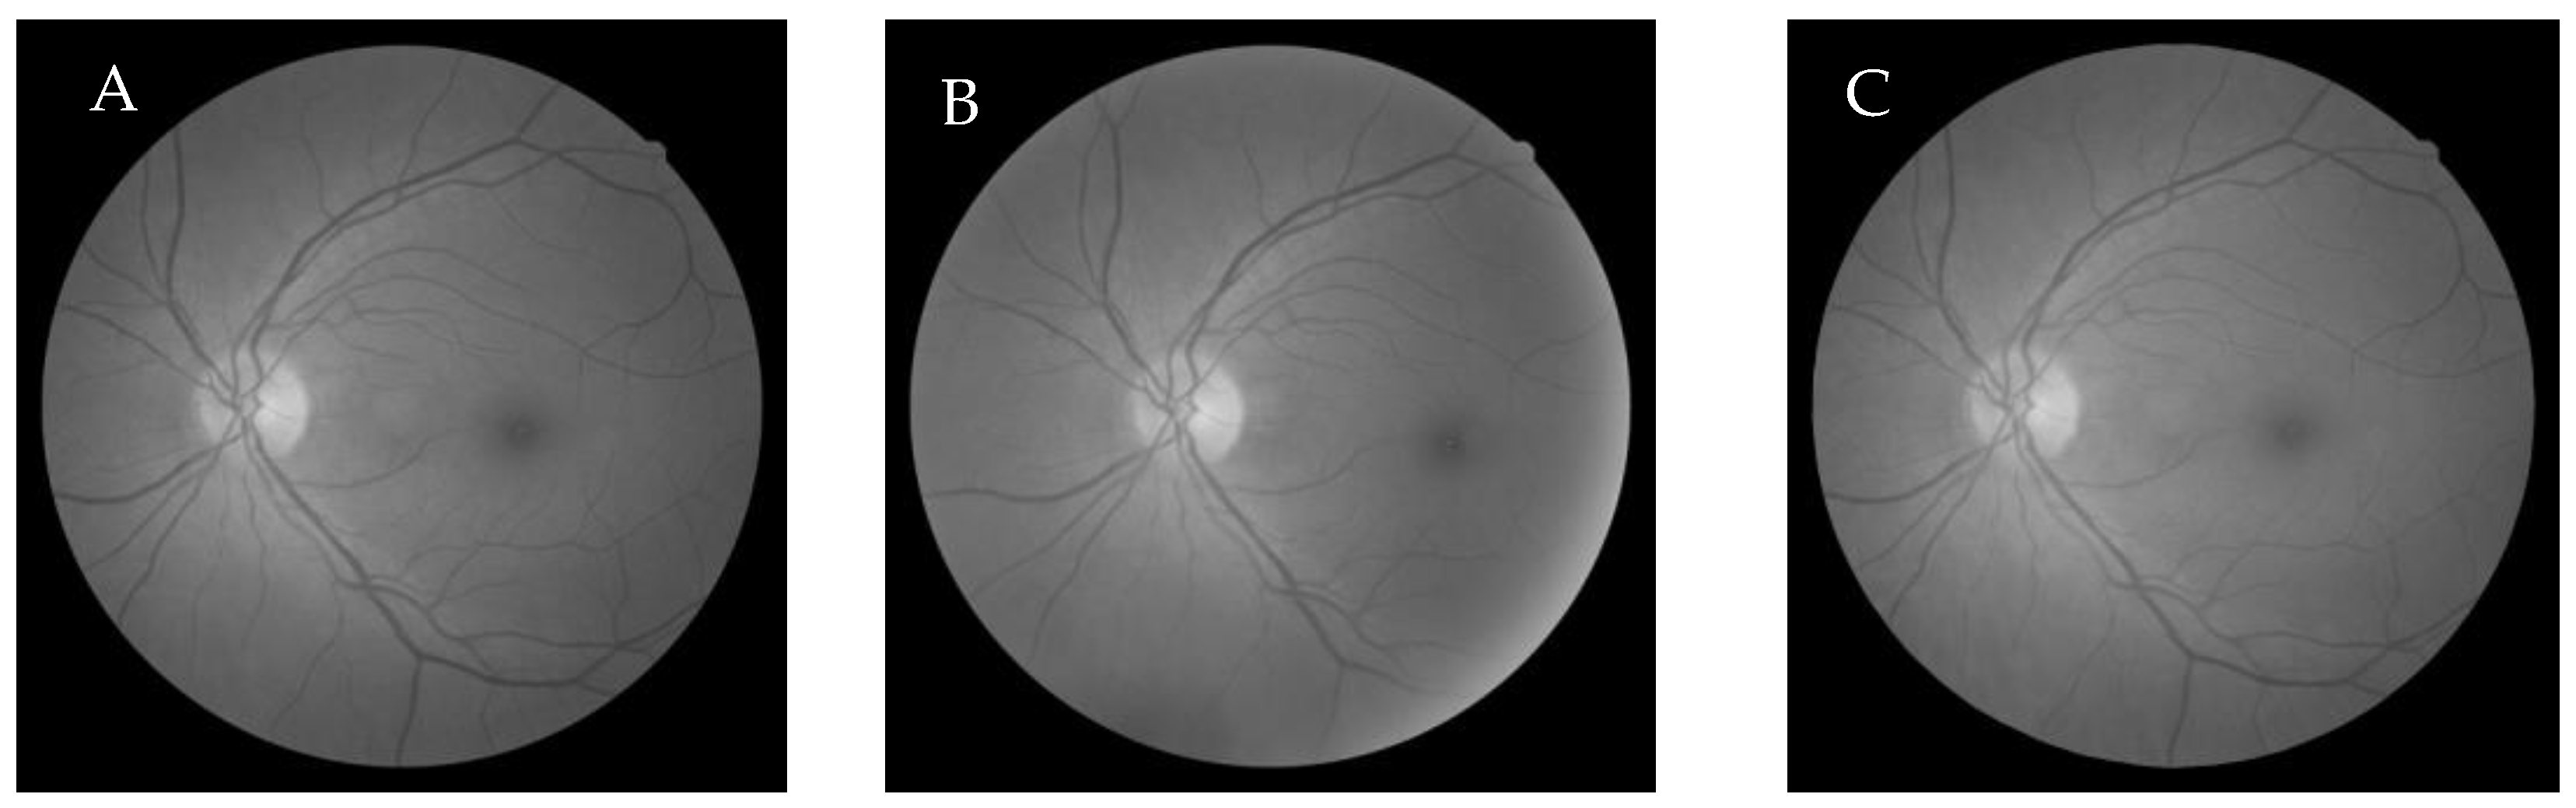

6.2.3. Cuckoo search algorithm-based Wang’s Demons registration